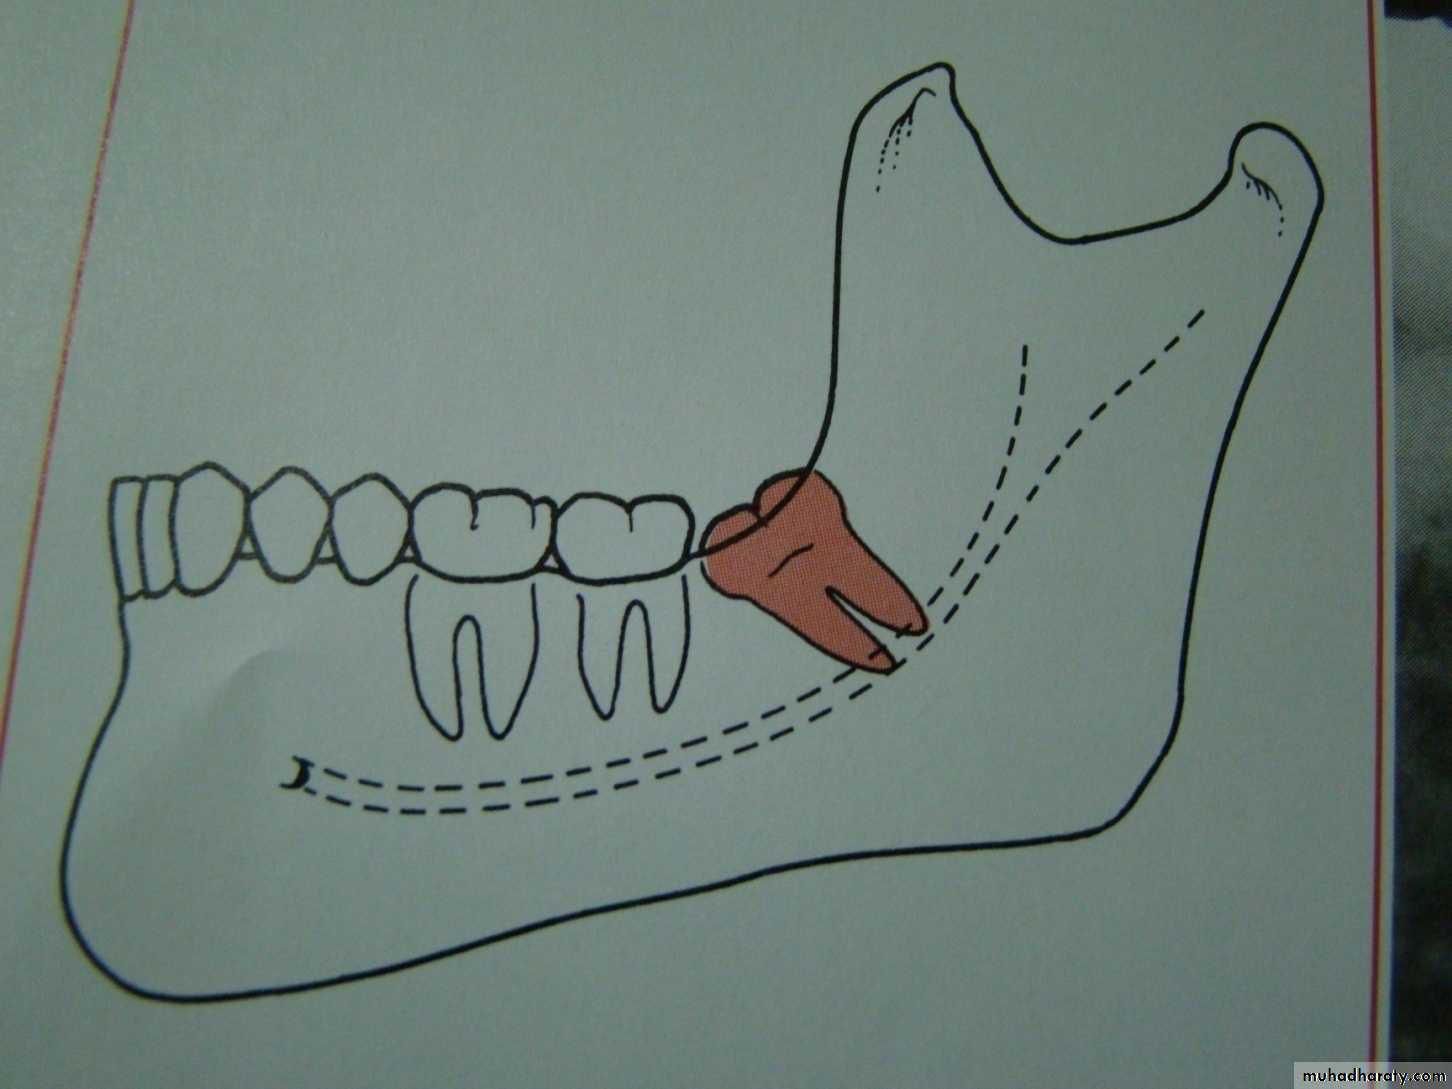

1- Pell and Gregory classification according to the depth or according to the relation of the impacted tooth to the occlusal plane of the lower second molar2- Pell and Gregory classification according to the relation ship of the lower second molar to the anterior border of the ramus

Relation of the impacted tooth to the anterior border of the ramus

Class 1 : the space between the lower second molar and the anterior border of the ramus is sufficient to accommodate the mesio distal dimension of the crown of the impacted lower third molarClass 2 : the space between the lower second molar and the ramus is insufficient to accommodate the crown of the impacted tooth .so part of it in the body and the other part lie in the ramus .

Class 3 the anterior border of the ramus lie near the distal surface of the lower second molar ,so ,the whole impacted tooth lie within the ramus .

Impacted tooth in relation to the ramus